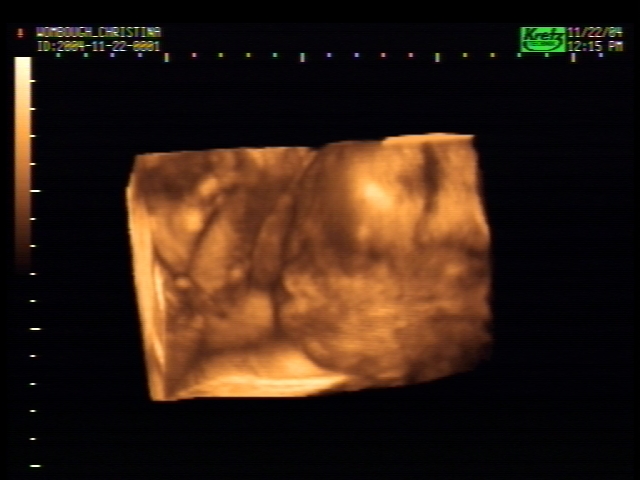

3D Sonogram Pictures